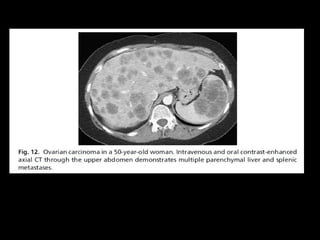

TC - TC

OVÁRIO

• Importante avaliação pré-operatória

• Avalia metástases (fígado, baço)

• Boa resolução para detectar 50% dos implantes

peritoneais quando >1cm de diâmetro

• S– 73% / E – 82%

• Melhor que RM na avaliação de implantes

calcificados

• Avalia recorrência ( usado como seguimento)